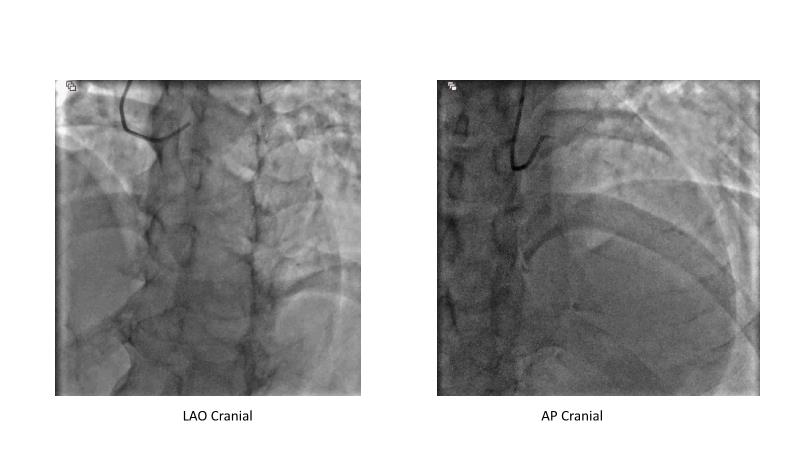

This session is recommended for you if you are seeking insights into the advantages of using IVUS imaging over visual assessment for better outcomes in left main bifurcation procedures. Discuss with experts the benefits of using RotaCUT in lesion preparation for left main bifurcation and explore the impact of high radial strength stents on the procedure's success.

• To understand why the use of IVUS imaging is different from seeing with experienced eyes to achieve improved left main bifurcation outcome